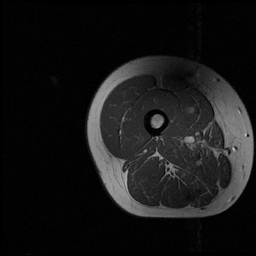

4.3 Results for thigh muscle MR images

Accurate segmentation of various thigh muscles plays a vital role in assessing musculoskeletal disorders like osteoarthritis. However, this task is difficult because of unclear boundaries and the similar intensity and texture among the muscles. The segmentation partitioned the thigh region into four main clusters: the quadriceps, hamstrings, other muscle groups, and remaining tissues. An example muscle MRI is presented in Fig. 5. Thigh muscle MR images contains 75 slices, each sized at 256×256256\times 256. In our experiments, 45 labeled exams are used for training, with the remaining 30 reserved for validation. The training dataset includes nn fully annotated images, with pixel-wise labels unavailable for the remaining 45n45-n. Table 2 provides the results. Fig. 6 illustrates the segmentation outputs produced by various models. As shown in Fig. 6, other methods struggle to accurately distinguish between different muscle categories. In contrast, the segmentation produced by our method aligns more closely with the ground truth and differentiates each muscle category more precisely, avoiding inter-class segmentation errors.

Refer to caption

Figure 5: Example T1-weighted thigh MR image. Left: original image. Right: expert-annotated segmentation with distinct colors indicating quadriceps (blue), hamstrings (red), and other muscles (green).